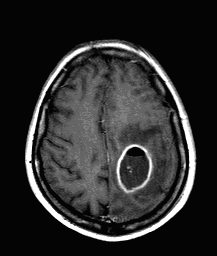

CT can usually lead to definitive diagnosis regarding brain tumors. A non-territorial localization (as opposed to arterial occlusion) of a usually “glove” shaped perifocal hypodense zone is highly suspicious for a tumor.

MRI provides even more definitive proof. On T1 weighed images they are usually hypointense, on T2 weighed images their signal is strong. Although these signs are very characteristic, normally they are still insufficient for exact differential diagnostic criteria.

Contrast enhancement of tumors, specific forms of enhancement:

Intravenous contrast agents (iodinated contrast media in CT, or chelated Gadolinium in MRI) normally do not pass over the blood-brain barrier. Contrast material cannot leave the blood vessels towards the parenchyma (secondary to its strong triple layer defense).

Therefore, where contrast enhancement is seen, the blood-brain barrier is damaged. This is only possible in intra-axial brain tumors, inflammatory states, certain types of demyelinating diseases (multiplex sclerosis) and at certain states in ischemic infarcts.

Low-grade astrocytomas typically do not enhance. A more pronounced enhancement is seen in a gliomas and it reflects their malignancy. This also means that if a low grade glioma during a follow-up study suddenly changes its enhancement pattern, the increase is regarded as a sign of malignant transformation.

In more advanced stages of abscess development (“mature” abscess, early capsule phase) the central hypodensity deepens further, the rim of enhancement becomes better defined and thin. The multilocular appearance is also possible. A slight vasogenic edema is seen outside the enhancing rim of the abscess.